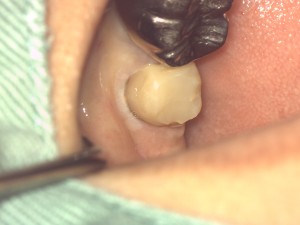

術前の写真です。コンポジットレジンで土台を作りましたが。虫歯が深いので被せた場合土台ごと脱落する可能性が大きいです。

このような場合フェルールが必要で、これを作ることによりクラウンがより強固になり長持ちします。

クラウンの辺縁は必ずご自分の歯に被せなければならないという原理原則があります。